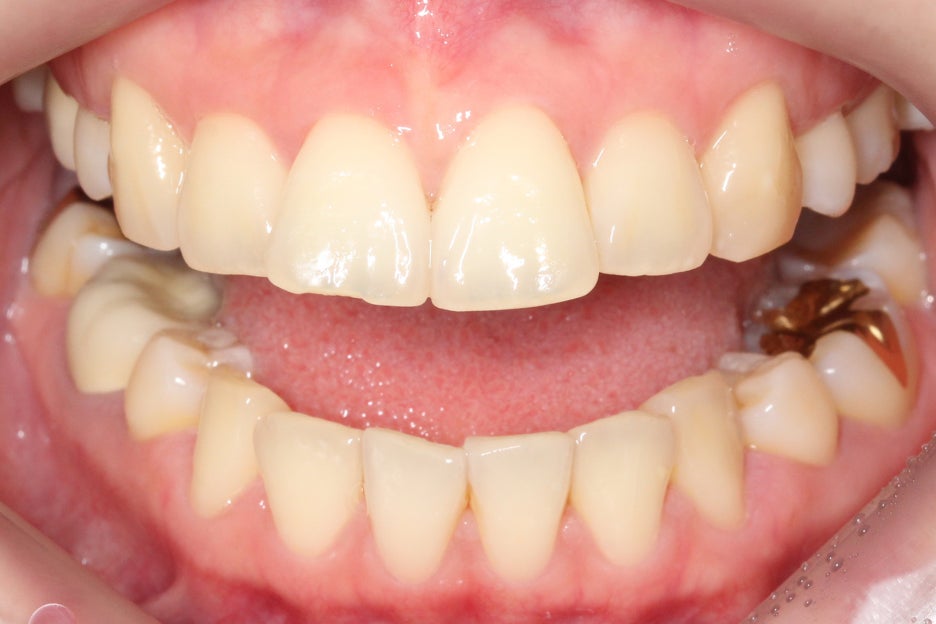

상하악을 개방하였을 때

보이는 아랫니의 배열도

앞쪽의 치열이 유난히

삐뚤거리는 상황인데요,

overbite 사진을 참고해보면

#11, #21 치아의 뻐드러짐과

돌출로 인해 전치부 교합이

잘 맞지 않는 모습을 확인할 수 있습니다.

아랫니의 돌출감도 상악에 비해

비교적 덜한 편이지만

치아 교정을 통해 개선할

여지가 있는 모습이네요.